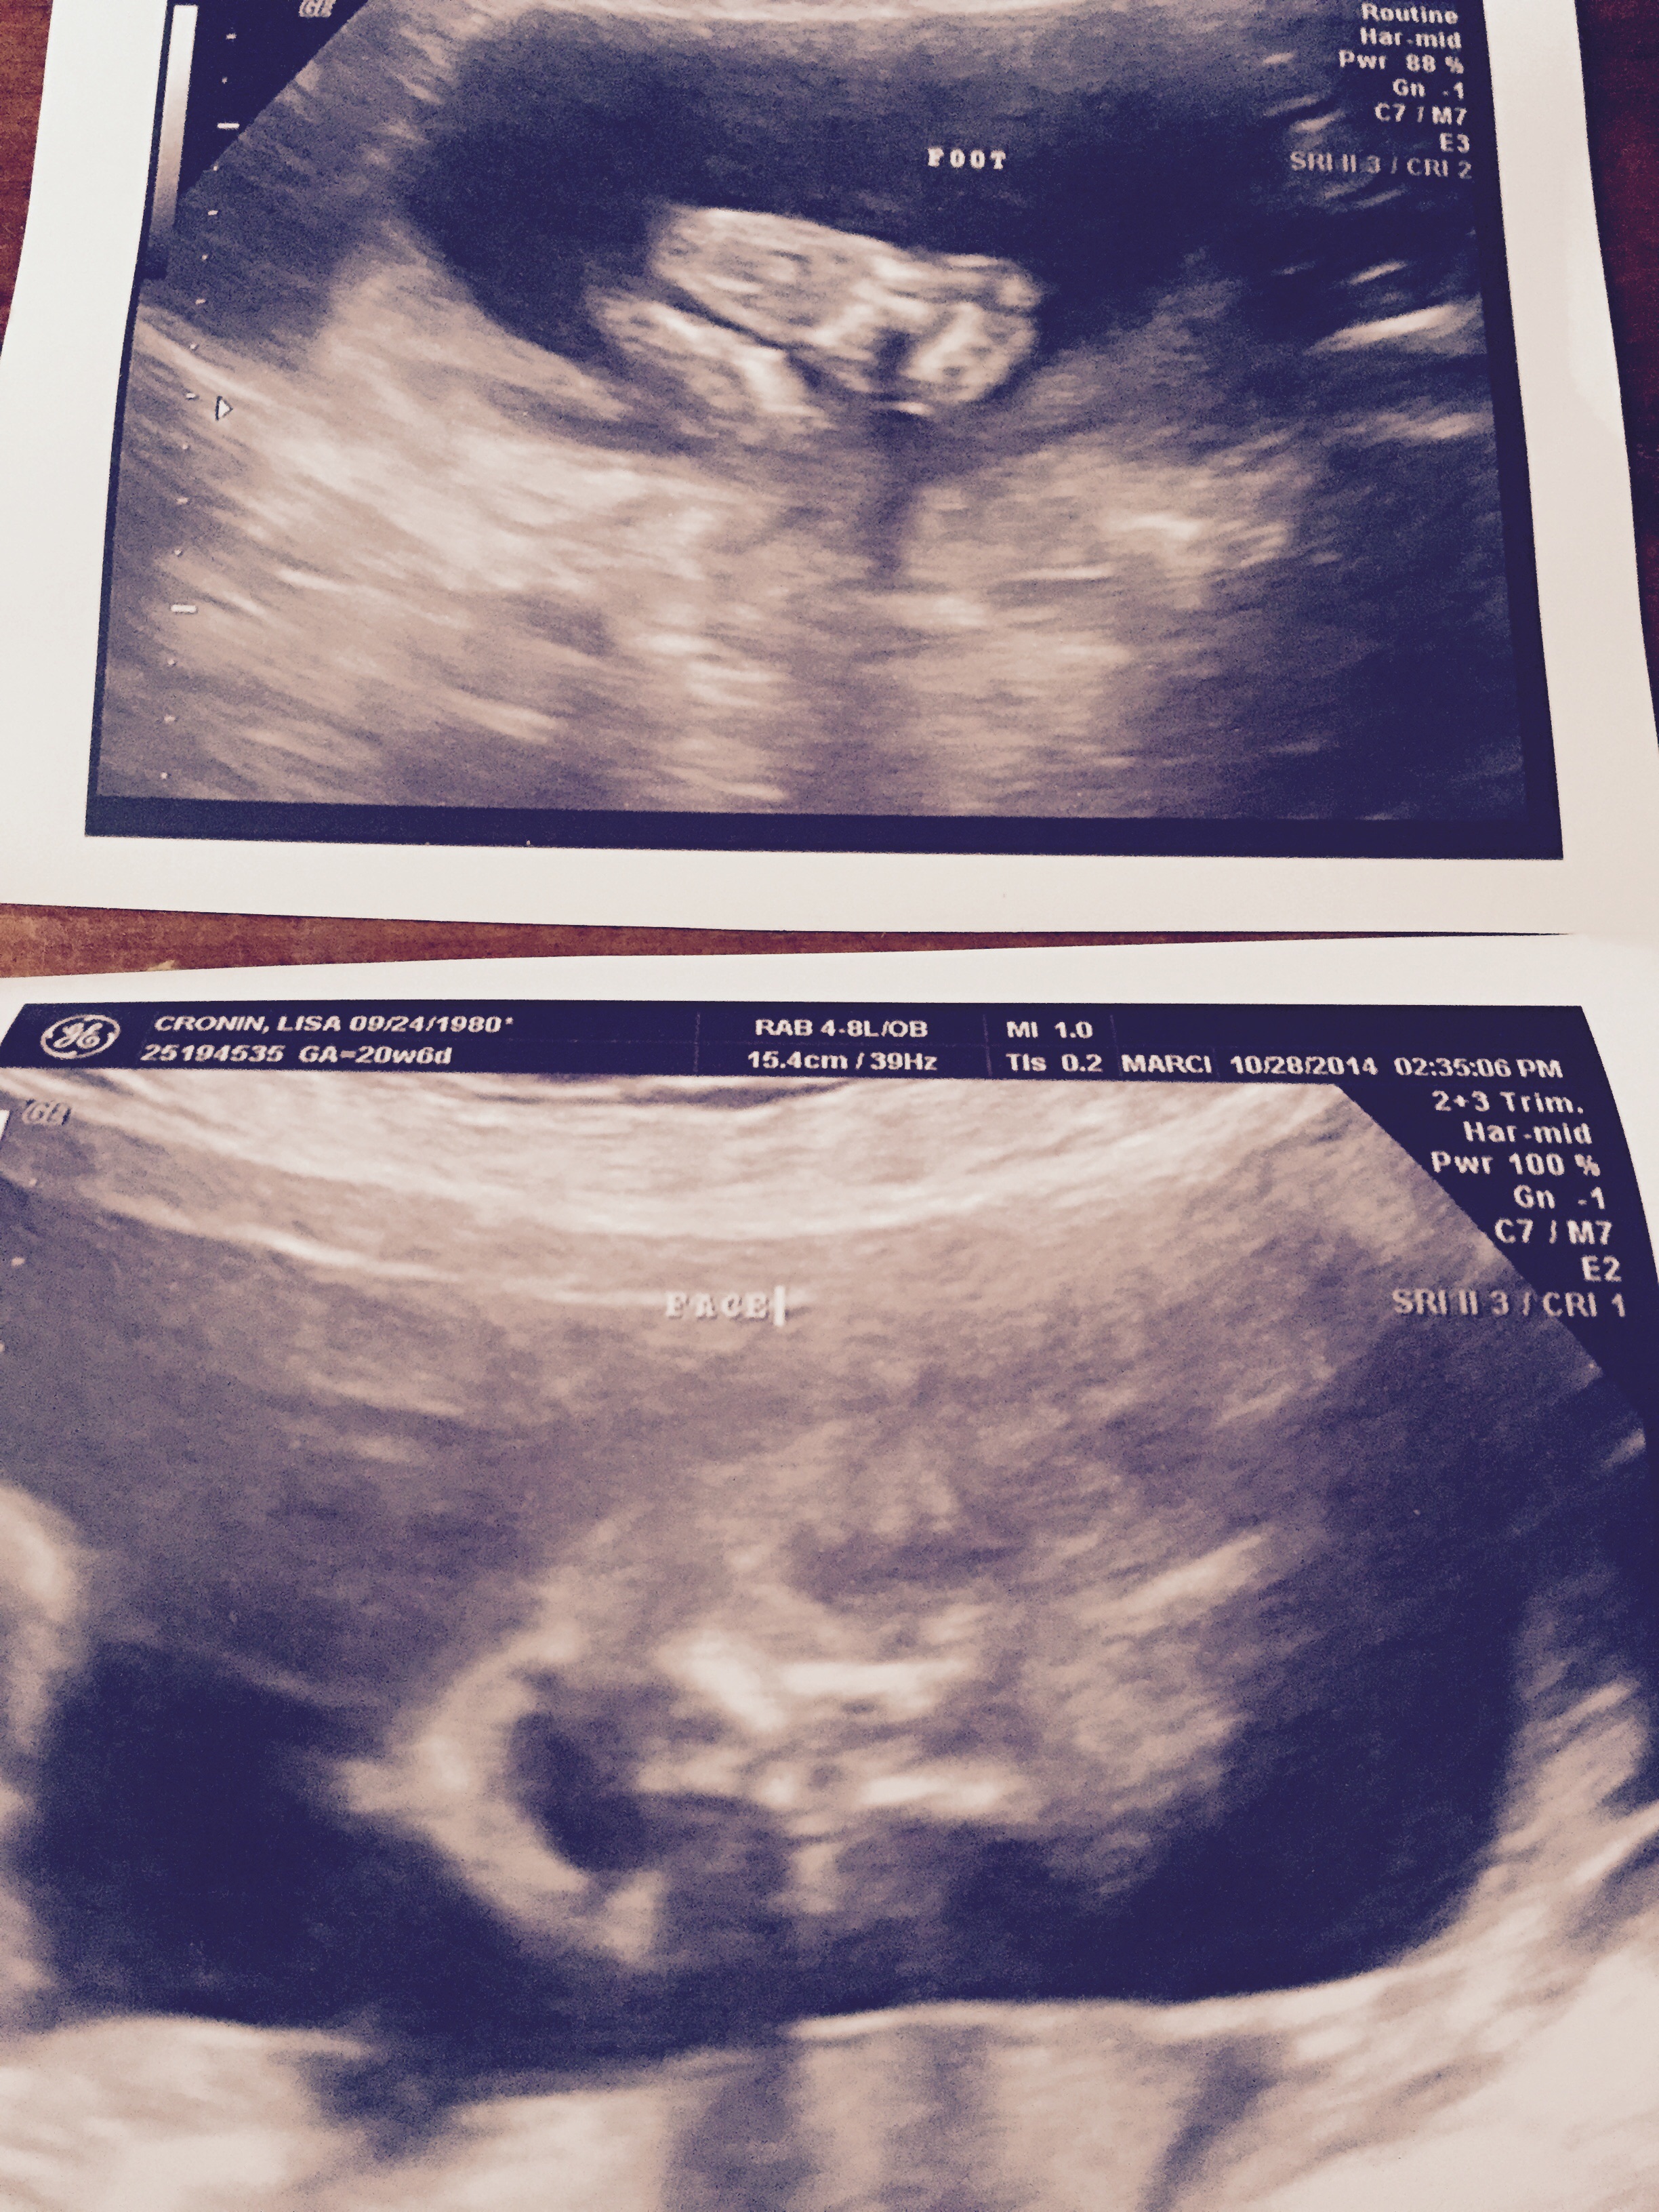

DH, SS, and I are over the moon to find out we are having a boy I was hoping for a girl, so we would have one of each, but I am just so so happy about my little boy I won't post his penis picture, but I will show you his cute face and feet ❤️

I was hoping for a girl, so we would have one of each, but I am just so so happy about my little boy

I won't post his penis picture, but I will show you his cute face and feet ❤️